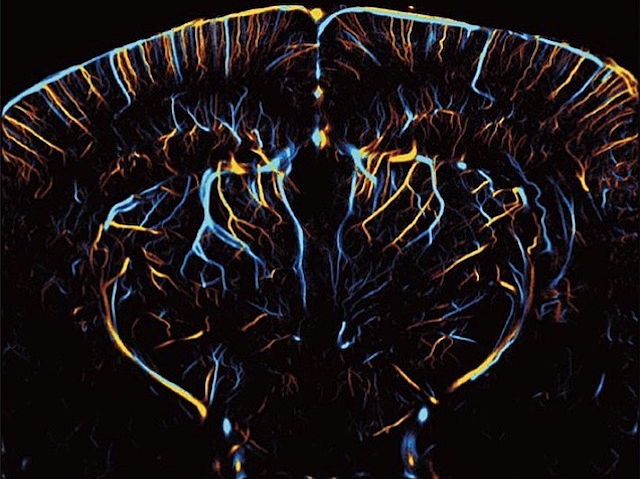

26 d'octubre de 2025Pensament en ProfunditatQuan fem exercici, la sang es posa en moviment. Però no només quan fem servir els músculs. Quan el cervell treballa intensament, ja siga resolent problemes o prenent decisions, augmenta el flux sanguini cap a les seues regions més actives. Per això, observar com circula la sang al cervell pot revelar quines zones estan actives en cada moment. Aconseguir-ho en els vasos sanguinis situats en zones profundes del cervell ha estat un repte, però ara és possible en ratolins anestesiats gràcies a la microscòpia de localització per ultrasons (MLU). Tot i això, l’anestèsia altera el comportament dels vasos, ja que els dilata i augmenta el flux de sang, cosa que pot distorsionar els resultats. Per això, els investigadors han desenvolupat una nova plataforma d’imatge cerebral amb MLU (a la imatge) que manté el cap del ratolí despert en una posició fixa, permetent registrar el flux sanguini tant per les venes (en blau) com per les artèries (en groc). Aquesta tècnica permet estudiar la circulació cerebral en animals desperts, sense els efectes de l’anestèsia, cosa que podria interferir amb els seus resultats. Escrit per Lux Fatimathas

Imatge del treball de Yike Wang i col·laboradors/es

Beckman Institute for Advanced Science and Technology, University of Illinois Urbana-Champaign, Urbana, IL, EUA

Publicat en eLife (reviewed preprint), octubre de 2025